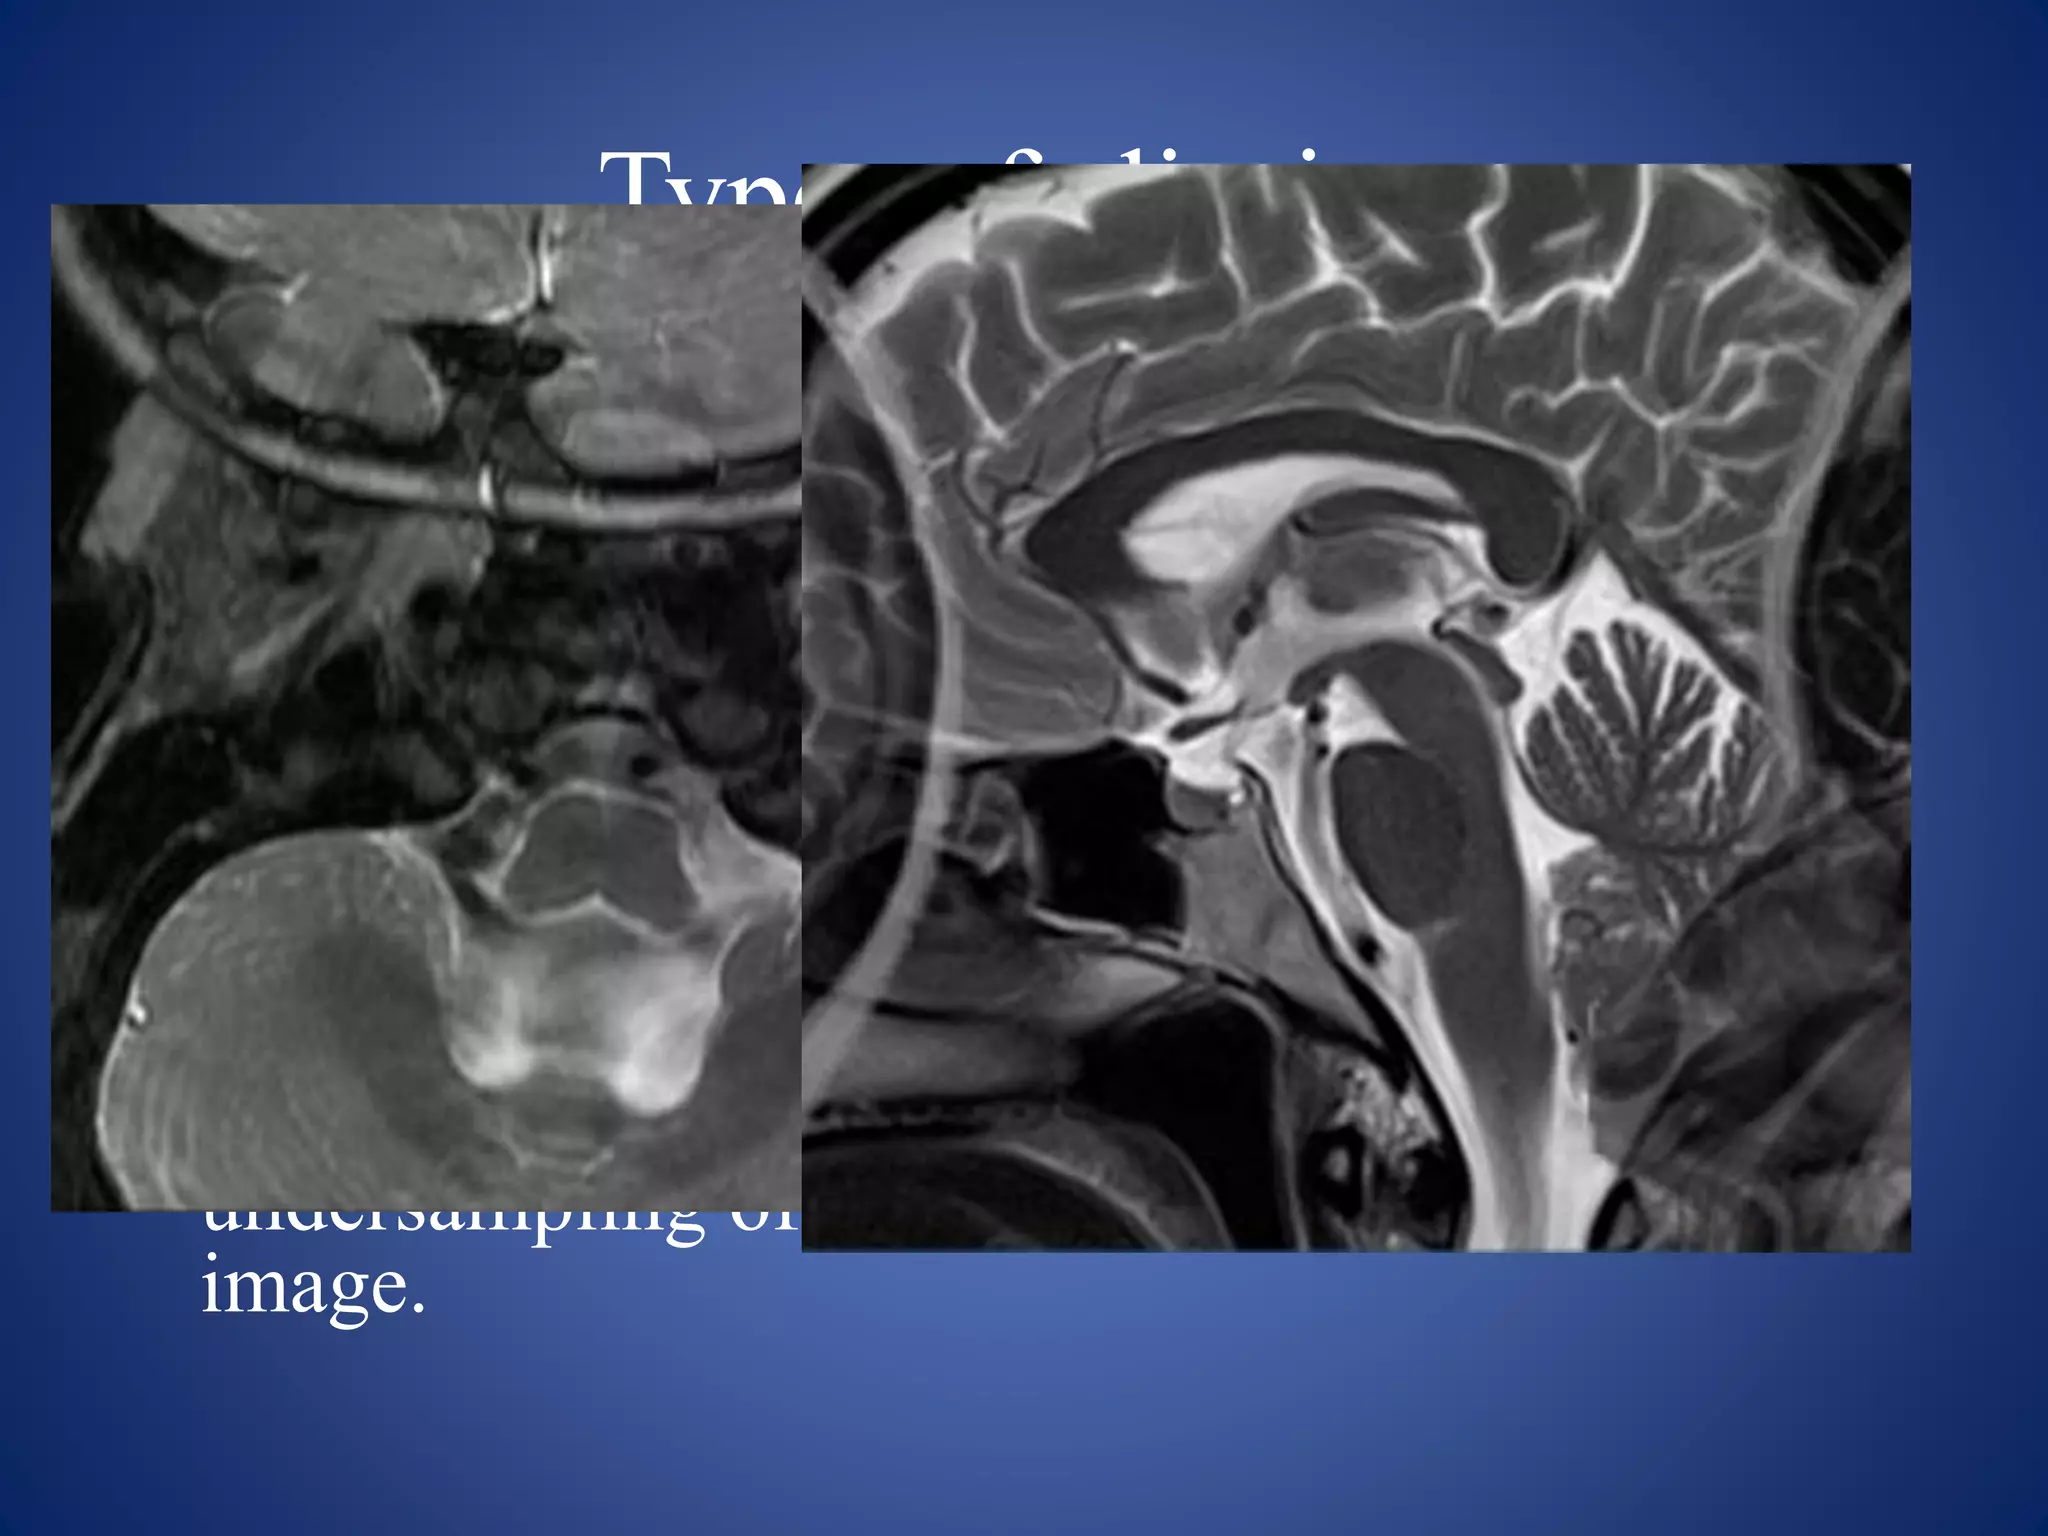

1.Truncation artifact

• Appearance: appears as a banding artifact at the

interface of high and low signals. It creates the low

intensity band running through high intensity areas.

• Causes:

• results from undersampling of data (too few k-space

lines are filled) so that interfaces of high and low signal

are incorrectly represented on the image.

• is most common when tissue is still producing a high

signal at the end of data collection or when the peak of

the echo is not centered in the middle of the sampling

window.

Remedy

• Undersampling of data should be avoided.

• Phase matrix should be increased. For example,

use a 512 × 512 matrix instead of 512 × 128.

• Techniques that partially fill k spaces should be

avoided

• Fat suppression techniques used in T1-weighted

imaging might reduce this artifact by nulling high

signal from fat at the beginning and end of the

sampling window.

• filters can be used that force the signal amplitude

to zero at the end of the sampling window